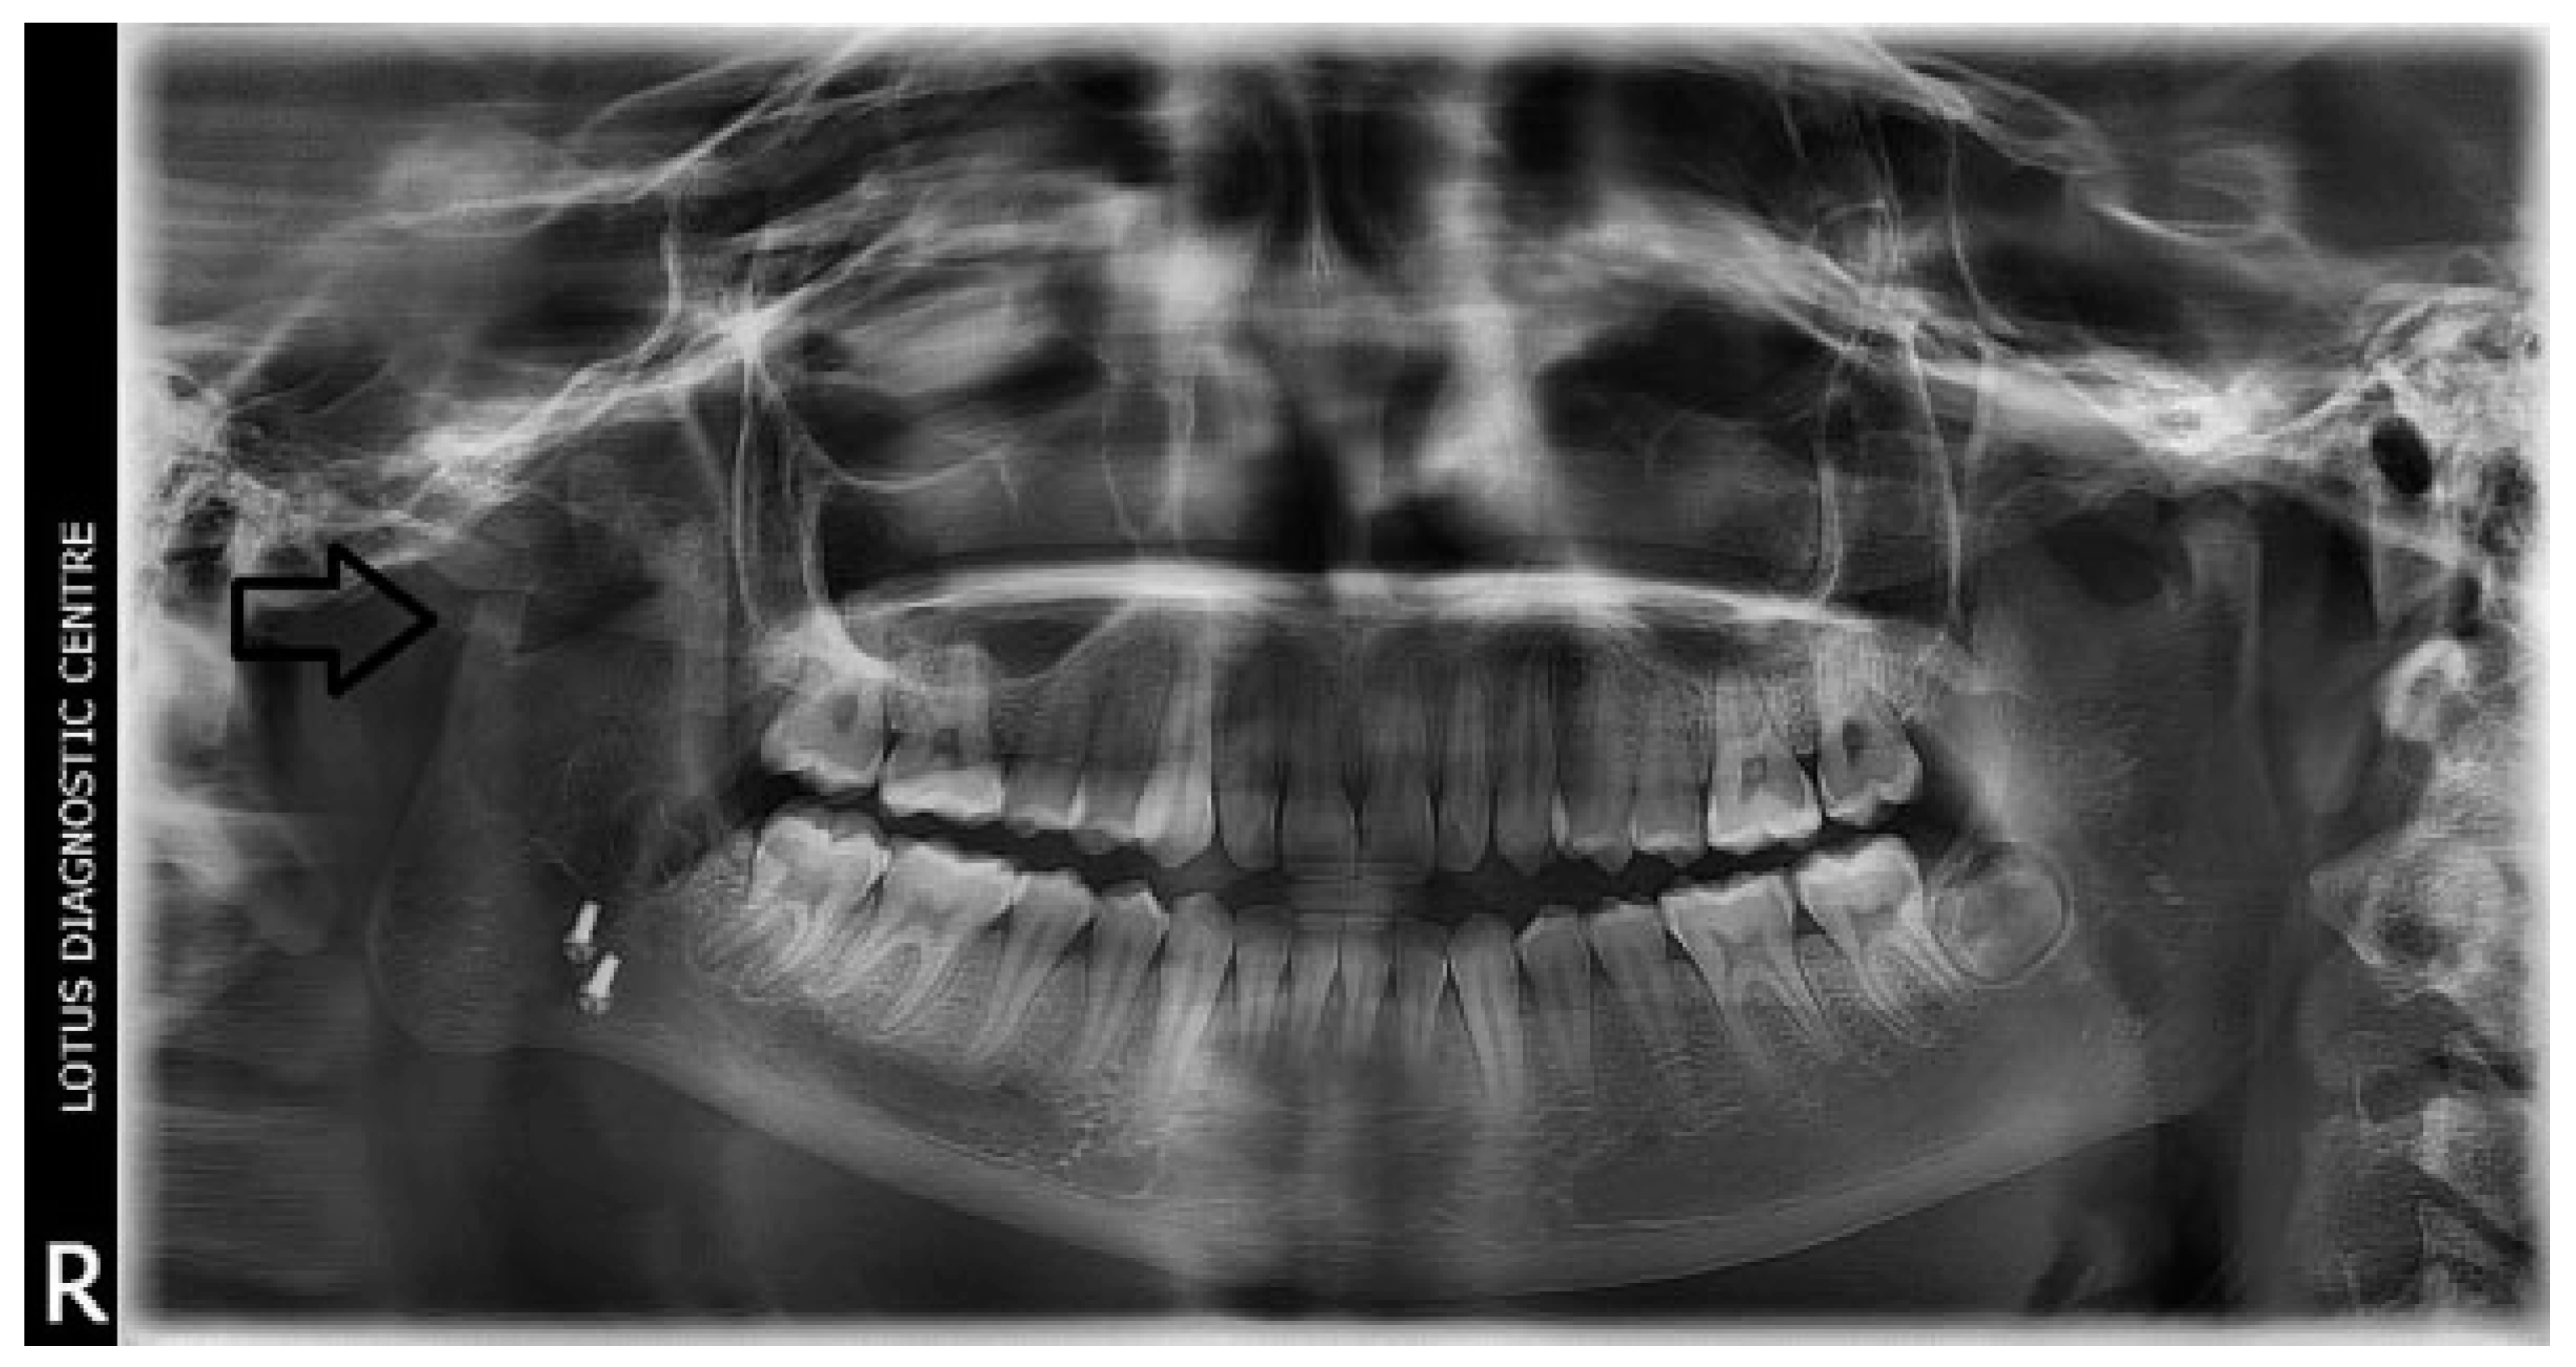

A retrospective study of post–ankylotic TMJ reconstruction of all the patients who underwent surgery for the TMJ ankylosis over a period of 11 years from 2002 to 2013, which were operated by the senior author (Y.B.), was undertaken to evaluate demographics, type of TMJ ankylosis, and modality of post–ankylotic TMJ reconstruction. The following inclusion criteria were considered for enrolling patients in this study: (1) history of traumatic injury to the face or jaws; (2) clinical and radiographic evidence of bony ankylosis at the time of presentation; (3) reconstruction of the TMJ using autogenous or alloplastic material after surgical release of ankylosis. Patients were assessed for (1) maximum interincisal opening pre and post operatively; (2) restored vertical ramal height; (3) occlusion; (4) facial symmetry; and (5) postoperative complications. Radiographic evaluation consisted of both preoperative and postoperative panoramic radiography Orthopentomogram (OPG) (Figure 1 and Figure 2) and CT scans in axial, coronal, and sagittal sections with three-dimensional reconstruction (Figure 3 and Figure 4). Surgical protocol was that the TMJ was approached through the Al-Kayat and Bramley’s incision and at least 2 to 2.5 cm resection of the ankylotic chunk was performed in all our cases. Ipsilateral and contralateral coronoidectomy was performed when required to achieve passive mouth opening. Interpositional arthroplasty was done using various materials such as temporalis fascia, temporalis muscle, and articular disc, whereas joint reconstruction was done using CCG and titanium reconstruction plate with condylar head. Intensive physiotherapy postoperatively was an integral part of protocol.

Temporalis muscle was used in seven patients and temporalis fascia was used in two patients. In our series, using temporalis fascia as an interpositional material in the postoperative MIMO was 37 mm. Temporalis fascia has the disadvantage of being thinner, taut, and nonelastic. Long-term follow-up showed premature contact of teeth on the operated side in both the patients and the ramal height was not maintained. When the temporalis muscle was used as interpositional material, we based our flap on one of the branches of deep temporal arteries to maintain its vascularity and the flap was turned over the zygomatic arch and placed into the glenoid fossa. Temporalis muscle provided us with more bulk to obliterate the joint space and was sandwiched between the chondral end of the CCG and temporal bone. After appropriate positioning has been established, the muscle is sutured in both the anterior and posterior directions. Moreover, there is no hematoma formation and hence had better long-term stability. In patients where temporalis muscle was used, the MIMO was 41 mm and ramal height was maintained in all the cases (Figure 7 and Figure 8). The ramal height was preserved in most of our cases possibly due to unilateral ankylosis with compensation by the contralateral mandibular unit. Management of ankylosis in children can be very challenging and our aim was to correct retrognathia in bilateral cases and reduce the possibility of further asymmetry in unilateral cases. Growth center transplantation using CCGs was done in seven growing children in the 6- to 13-year age group. The uses of this biologically compatible autograft in reconstruction are benefits of growth potential and ability to remodel into a neocondyle with time. Unpredictable growth pattern of the CCG, midline shift, and donor site morbidity are some of the disadvantages of this technique. Overgrowth of the graft has been attributed to the use of a large cartilaginous cap; hence, only 1 to 2 mm cartilaginous cap must be used to avoid such complications [13,14,15]. We assessed the same using panoramic radiographs during follow-ups. The CCGs showed excellent mandibular growth along with complete integration of graft into the recipient site over the passage of time in all seven cases. The CCG was harvested from the sixth rib (contralateral side) using submammary incision and was secured using three 2-mm titanium screws at the recipient site. Due to the close proximity of the chondral cartilage to the base of skull, we routinely interposed temporalis muscle in these patients. The muscle pedicle acted as an artificial disc as well as a barrier between the base of skull and chondral cartilage (Figure 9). Early and vigorous mobilization is important to prevent postoperative adhesions and reankylosis [16]. The postoperative MIMO in seven patients was 41.5 mm. Asymmetry in the form of deviation of chin was found in one patient during long-term follow-up, where CCG overgrowth led to the deviation of the chin to the contralateral side.

The unique ability of the CCG to remodel into neocondyle could be well appreciated on the digital OPG and CT scan of the patient. The length and width of the neocondyle was very much comparable to the length of the condyle on the unaffected side at 6 years follow-up. Thus, the neocondyle formed using the costochondral cartilage was identical to the unaffected mandibular condyle both structurally and functionally. Poor socioeconomic conditions and lack of awareness coupled with poor primary health care facilities lead many of these unfortunate patients to live with this debilitating condition well into adulthood. Five such adult patients with age ranging from 17 to 36 years reported to us for treatment of TMJ ankylosis. In all these patients, ankylotic bony mass extends beyond the boundaries of the joint capsule. Alloplastic reconstruction after the release of ankylosis was our method of treatment, although high cost of condylar prosthesis led us to use 2.4 mm condylar head reconstruction plate along with temporalis muscle interpositioning in these patients. Interpositional grafts may fail to restore the ramal height in bilaterally ankylosed adult patients, so alloplastic condylar reconstruction may become the preferred choice. Advantages of alloplastic TMJ reconstruction are that the physical therapy can begin immediately, there is no need for a secondary donor site, surgery time is decreased, and alloplasts can be constructed in such a way as to mimic the normal anatomic contours of the structures they are to replace [17,18]. Wolford and Karras have suggested autologous fat transplantation as a useful adjunct to prosthetic TMJ reconstruction, as it minimizes the occurrence of excessive joint fibrosis, heterotopic calcification, and improves the range of motion [19]. However, they have categorically stated in their discussion that heterotopic bone formation is seen in multiple operated joints and joints with previously failed alloplastic implants. Another method to combat heterotopic bone formation is the use of 10 Gy of irradiation in five fractionated daily doses in the immediate postoperative period [20]. In our series, none of the patients reported with heterotopic bone formation possibly because they had undergone a single surgical procedure for managing TMJ ankylosis. The risk of fossa perforation could have been taken care by interpositioning of temporalis muscle in all these patients.

Figure 1. Preoperative OPG of right temporomandibular joint ankylosis.

Figure 2. Postoperative OPG at 6 years of follow-up (black arrow depicting CCG graft with temporalis muscle interpositioning with respect to right temporomandibular joint).